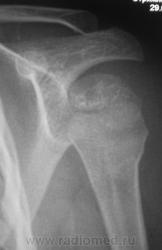

Но у первого пострадавшего помимо перелома и вывиха в плечевом ещё и надрыв/разрыв ключично-акромиального сочленения.

На мой взгляд, вывих спорный.

В обоих случаях перелом хирургической шейки плечевой кости. А почему только в одной проекции? Мы всегда снимаем в двух - в прямой и аксиальной.